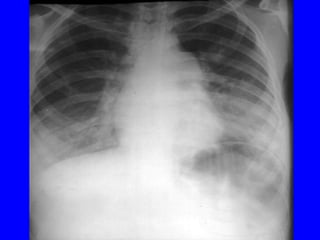

X quang phoåi:  xaùc ñònh , xñònh NN, ñoä naëng

VP thuyø, thaâm nhieãm phoåi, VP moâ keõâ

4.3 Chaån ñoaùn xaùc ñònh:

Laâm saøng: soát+ ho+ thôû nhanh vaø hoaëc co

loõm ngöïc

+ X quang: coù toån thöông phoåi: toån thöông

pheá nang; moâ keõ; toån thöông thuøy phoåi